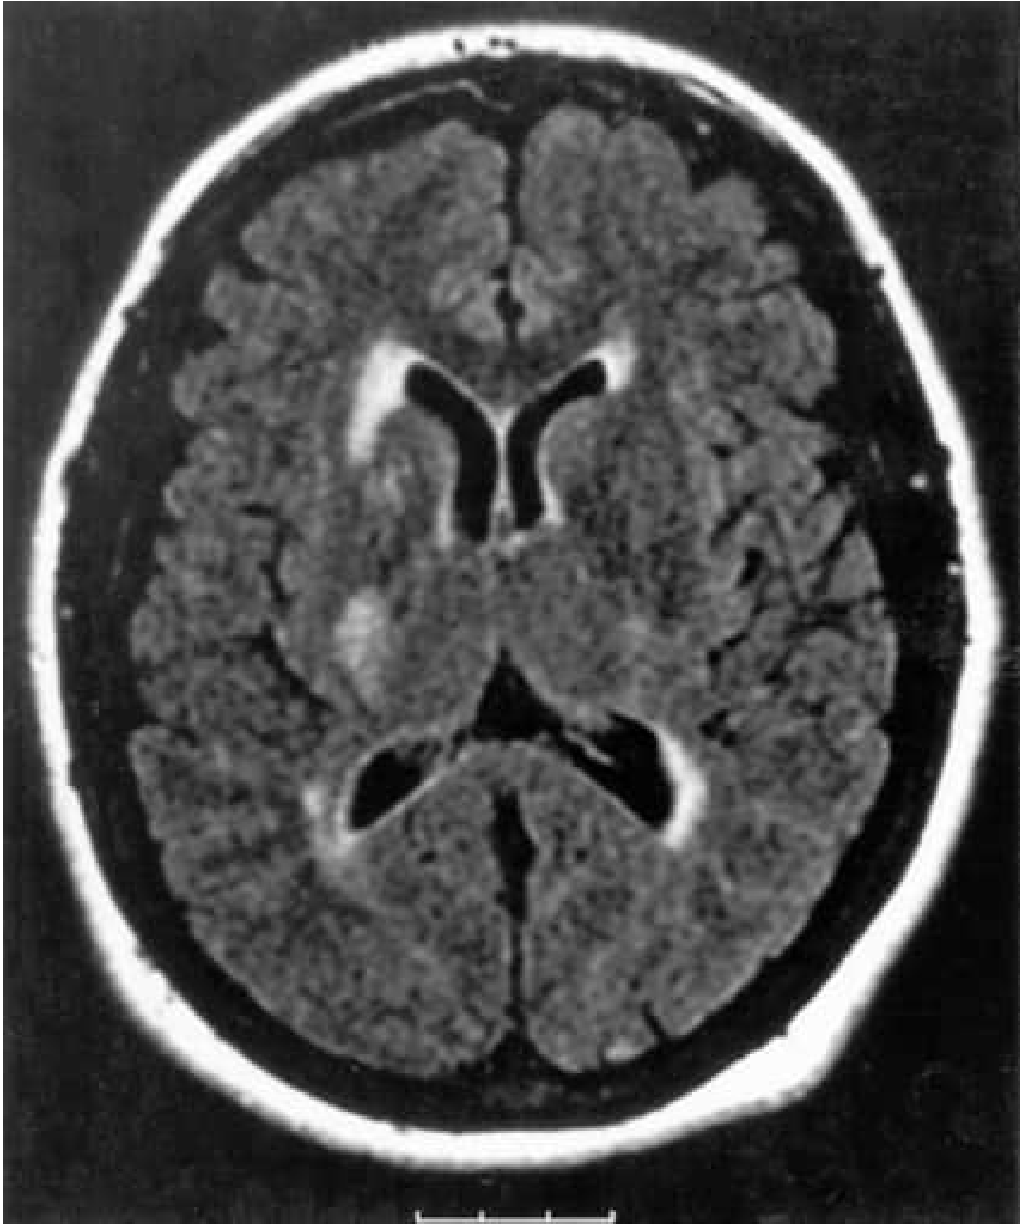

Axial FLAIR MRI showing infarction in the posterior limb of the right internal capsule in the anterior choroidal artery territory

Anterior choroidal artery territory infarct in posterior limb of internal capsule — Bradley and Daroff's Neurology in Clinical Practice

• Infarction in the posterior limb of the internal capsule (Fig. 65.15, shown below)